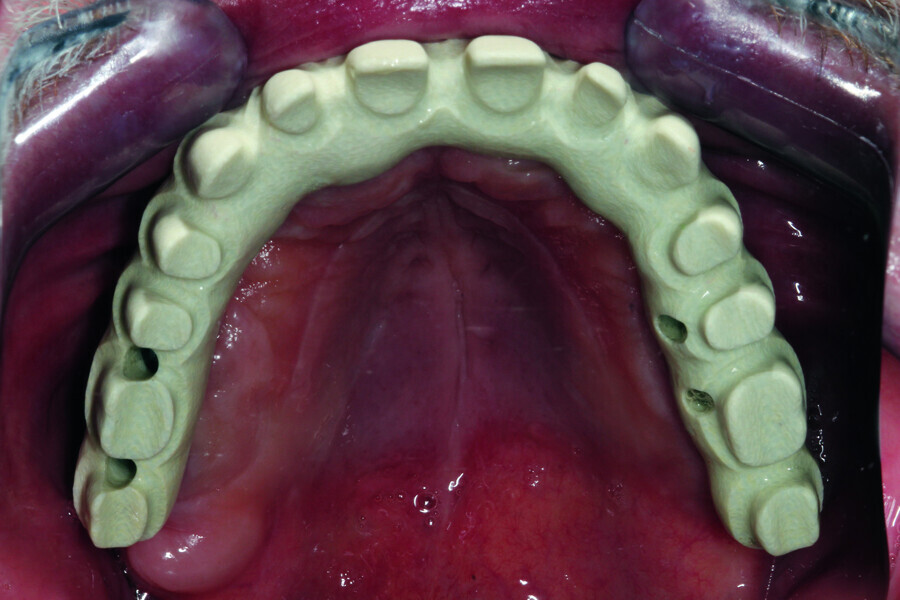

Fig. 5: Design of the framework visible from the palatal side. Visible abutments prior to the placement of telescopic crowns at the frontal section with abutments to be attached by

means of screws at the lateral section.